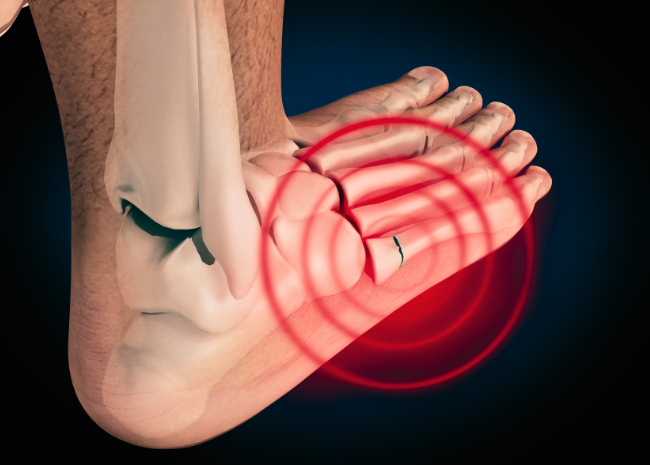

Treatment for metatarsal fracture outlet

Treatment for metatarsal fracture outlet, Jones Fracture Bunbury Foot Ankle Surgeon outlet

Treatment for metatarsal fracture outlet

Jones Fracture Bunbury Foot Ankle Surgeon

Metatarsal Fracture Broken Foot Bones Orthopaedic Trauma Association OTA

Product Name: Treatment for metatarsal fracture outlet5th Metatarsal Fracture Surgery Procedure Recovery outlet, Jones Fracture of the Foot Symptoms Treatment and Recovery outlet, Jones Fracture Symptoms Causes Treatment outlet, Metatarsal Fracture Broken Foot Bones Orthopaedic Trauma Association OTA outlet, Metatarsal Fracture Broken Foot Bones Orthopaedic Trauma Association OTA outlet, Metatarsal Fractures Foot Ankle Orthobullets outlet, 5th Metatarsal Fracture Motus Physical Therapy outlet, Metatarsal Fracture Broken Foot Bones Orthopaedic Trauma Association OTA outlet, Metatarsal Fracture Orange County Irvine Huntington Beach outlet, Foot Fracture Treatment Broward Palm Beach Florida Foot Ankle outlet, Clinical Practice Guidelines Metatarsal Foot Fractures Emergency Department outlet, Managing Foot Fractures in Urgent Care Journal of Urgent Care Medicine outlet, Metatarsal Fracture Causes Symptoms Treatments Surgery Recovery outlet, 4 Types of Fifth Metatarsal Fracture outlet, Foot Injuries Royal Cornwall Hospitals NHS Trust outlet, 5th Metatarsal Fracture Surgery Procedure Recovery outlet, Metatarsal Stress Fractures Gold Coast Physio Sports Health Ashmore Burleigh outlet, Metatarsal Fracture Treatment in Laguna Beach CA SCFAS outlet, The treatment process of metatarsal fracture using HP Mg screw red. Download Scientific Diagram outlet, Metatarsal Stress Fracture Doctor in St. Louis MO Missouri Foot Ankle outlet, Treatment of Fourth Metatarsal Base Fracture Non Unions in Middle Aged Women with Osteoporosis A Case Study The Foot and Ankle Online Journal outlet, Metatarsal Shaft Fractures FootEducation outlet, 5th Metatarsal Stress Fracture Treatment Management outlet, Metatarsal fracture Kingston Hospital outlet, Urgent Care Evaluation and Management Of Proximal 5th Metatarsal Fractures Journal of Urgent Care Medicine outlet, Broken Toes Fractured Toe Pain Foot Health Facts Foot Health Facts outlet, 5th Metatarsal Fractures Dr Hamish Curry Foot Ankle Surgeon outlet, Jones Fracture Bunbury Foot Ankle Surgeon outlet, Metatarsal Fracture Broken Foot Bones Orthopaedic Trauma Association OTA outlet, Fifth Metatarsal Avulsion Fractures The Jackson Clinics outlet, 5th Metatarsal Fracture Exercises Jones Fracture Rehab Exercises Foot Fracture Physical Therapy outlet, Treatment of Fourth Metatarsal Base Fracture Non Unions in Middle Aged Women with Osteoporosis A Case Study The Foot and Ankle Online Journal outlet, Metatarsal stress fracture Treatment with a Spring Plate MyFootShop outlet, 5th Metatarsal Fracture Treatment Private Surgeon London London Foot and Ankle outlet, Metatarsal Fracture in the Foot Ankle Foot Centers outlet.